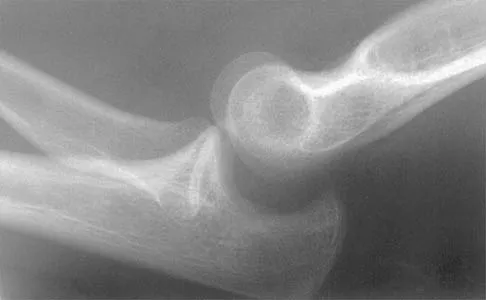

Figure 3 shows the radiographs of a 32-year-old man who fell 12 feet onto his outstretched arm and sustained a fracture-dislocation of the elbow. Initial management consisted of closed reduction of the dislocation. Surgical treatment should now include repair or reduction and fixation of the

Explanation

The radiographs show fractures of the coronoid and radial head. The medial collateral ligament has been avulsed from the ulnar insertion, and there is a valgus opening on the medial side. The lateral collateral ligament is always disrupted in elbow dislocations and fracture-dislocations that occur secondary to falls. This is known as the terrible triad injury (dislocation and fractures of the coronoid and radial head); it has a very poor prognosis because of its propensity for recurrent or persistent instability and late arthritis. The principle in treating this injury is to repair all of the injured parts or protect them with a hinged external fixator until they heal. Norris TR (ed): Orthopaedic Knowledge Update: Shoulder and Elbow. Rosemont, IL, American Academy of Orthopaedic Surgeons, 1997, pp 345-354. Kasser JR (ed): Orthopaedic Knowledge Update 5. Rosemont, IL, American Academy of Orthopaedic Surgeons, 1996, pp 283-294.